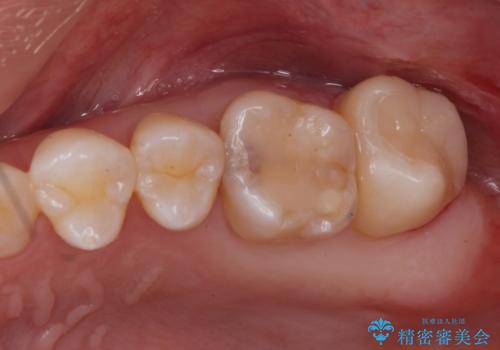

白い詰め物が入り、ザラザラもなくなりました。

一つ手前の古いプラスチックで治療されている歯も現在詰め物にやりかえを検討中です。